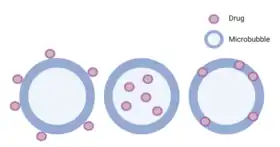

Microbubbles

Due to their ability to oscillate with exposure to low-frequency ultrasound, microbubbles have been used as contrast agents in order to visualize tissues in which the microbubbles have permeated.[44] However, when these microspheres are exposed to higher pressure ultrasound, they can rupture, which could be beneficial for drug delivery purposes.[44] Through SDT, these microbubbles could be selectively bursted at the tumor microenvironment in order to decrease systemic levels of the encapsulated drug and increase therapeutic efficacy. When applying SDT, the increase in acoustic pressure leads to the inertial cavitation, or collapse of the microbubble and local release of the cargo within. The inertial cavitation of the microbubbles when exposed to SDT is also referred to as ultrasound mediated microbubble destruction (UMMD).[45] The shell of microbubbles can be decorated with different components, including polymers, lipids, or proteins depending on their intended purpose.[44] Microbubbles have also been used for the localized release of attached cargo. This cargo is typically chemotherapeutics, antibiotics, or genes.[12] Different drugs can be directly loaded into the microbubble with methods such as conjugation and nanoparticle, liposome loading, and genes. The combination of genes and SDT is referred to as sonotransfection.[12] Examples of outer shell modifications can be seen in a study by McEwan et al. which found that lipid microbubbles showed reduced stability when sonosensitizers were added to their shells.[44] However, attaching the polymer poly lactic-co-glycolic acid (PLGA) to the shell resulted in increased stability compared to the lipid microbubbles without losing other desirable properties such as targeted delivery and selective cytotoxicity.[44] In another study, McEwan et al. investigated the ability of microbubbles carrying oxygen to increase production of reactive oxygen species, which are a necessary component of SDT, in the hypoxic environment of many solid tumors.[46] These microbubbles were stabilized with lipids and a Rose Bengal sonosensitizer was attached to the surface to treat pancreatic cancer.[46] Their work showed that coupling oxygen-loaded microbubbles that are sensitive to ultrasound with sonosensitizing drugs could allow for increased drug activation at the desired target even if hypoxia is present. Examples of therapeutics that have been loaded into microbubbles are gemcitabine, paclitaxel nanoparticles, plasmid DNA and 2,2′-azobis[2-(2-imidazolin-2-yl)propane]dihydrochloride loaded liposomes.[47][45][48][49] Due to the targeting nature of the ligands connected to the microbubble, it allows for the controlled and specific targeting of the desired tissue for treatment. Another study performed by Nesbitt et al. has shown improved tumor reduction when gemcitabine was loaded into the microbubble and applied to a human pancreatic cancer xenograft model with SDT.[48]